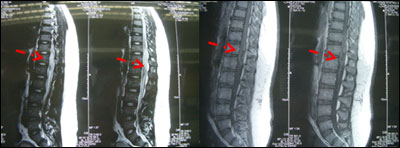

术前图片

急诊手术切除髓内肿瘤术后患者肌力较术前有所恢复,二便仍有障碍,出院后常规行外放射治疗。

术后图片:肿瘤大部切除。